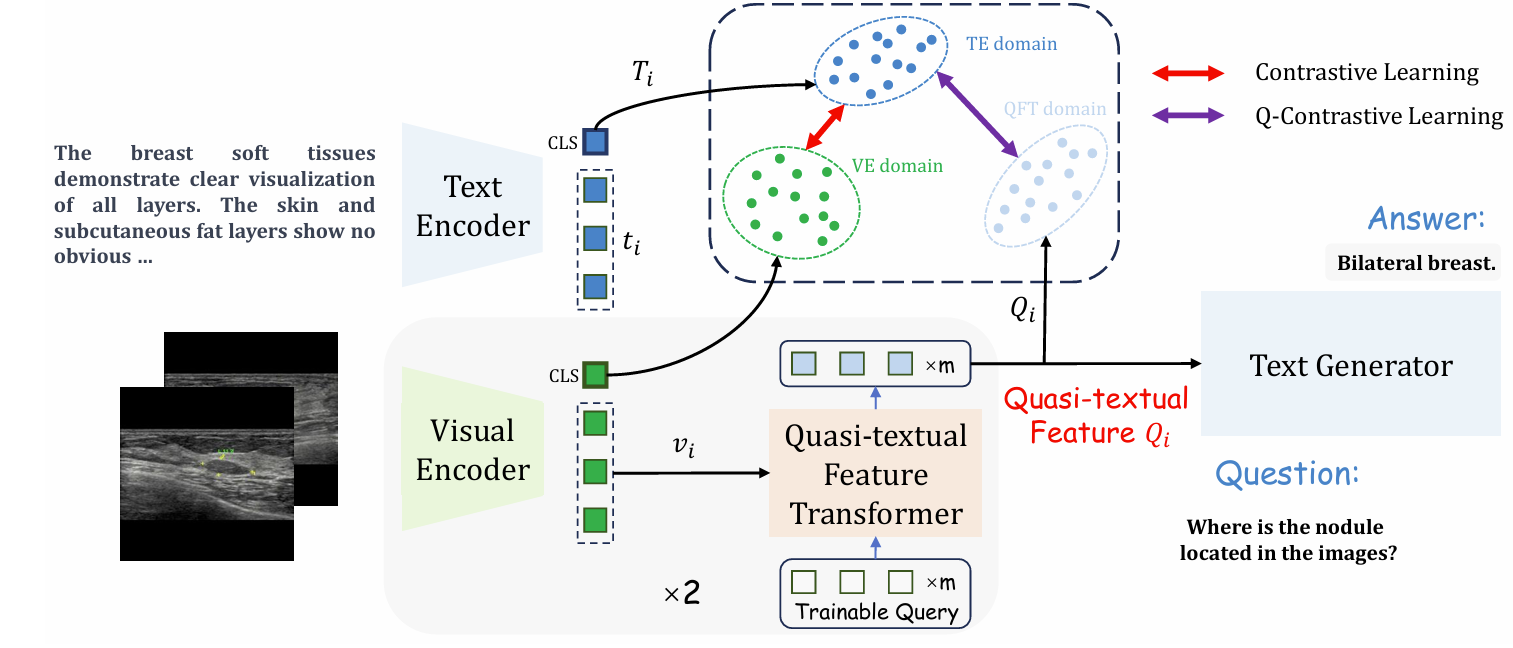

Jun Li, Che Liu, Wenjia Bai, Rossella Arcucci, Cosmin I. Bercea, Julia A. Schnabel.

[paper]

[project]

[huggingface]